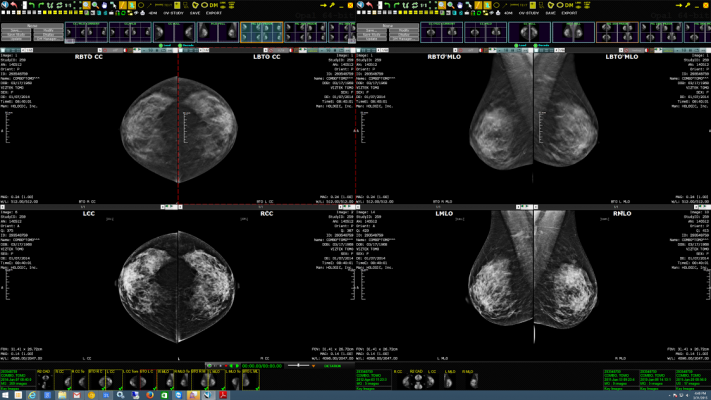

Exa Mammo: Debuted earlier this year, the system is the first to provide the benefits of a quality single workstation viewing and anywhere remote access for any breast imaging study including digital breast tomosynthesis (DBT). Radiologists benefit from the ability to read and compare breast images from any location within the department or offsite, regardless of the PACS they are using. The system is built on the Viztek Exa platform which offers two unique advantages - true Zero Footprint (ZFP) viewing and Server Side Rendering (SSR).